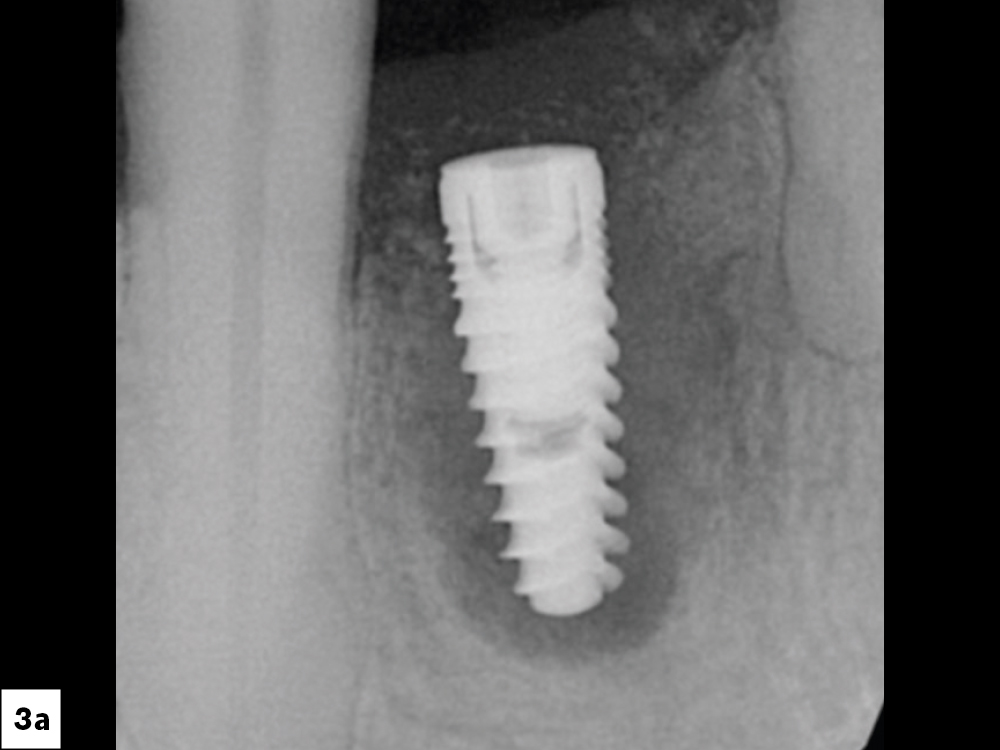

Recent meta-analyses and systematic reviews have reported a significantly higher risk of implant failure in smokers compared to non-smokers. A Medicina (Kaunas) study published in 2021 reported that implants placed in smokers had a 140% higher risk of failure than those placed in non-smokers, with a failure odds ratio of 2.4 for smokers.6 Similarly, a study published in the Annals of Palliative Medicine concluded that smoking patients have a 40% higher probability of implant failure compared to non-smoking patients (Fig. 3).7

Figures 3a, 3b: Implant failures associated with tobacco use.